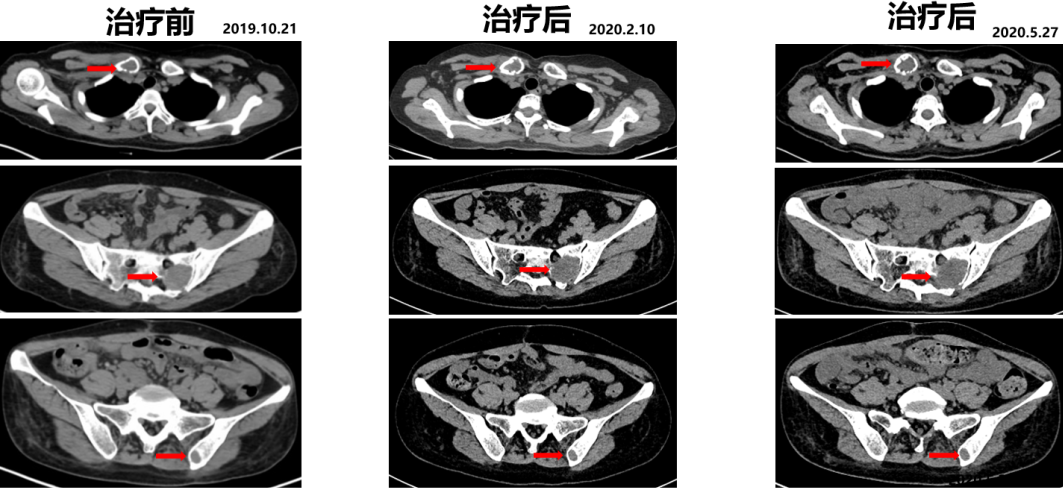

复查PET-CT:右侧锁骨、骶骨、及左侧髂骨局部骨质破坏并代谢活跃,考虑转移。

△PET-CT显示多处骨质破坏并代谢活跃

2019.10.21开始舒尼替尼50 mg po QD治疗(4/2方案)。

2020.05.27复查PET-CT病灶稳定,代谢较治疗前明显减低。影像学评估SD。

△舒尼替尼治疗后病灶稳定,代谢较治疗前明显减低